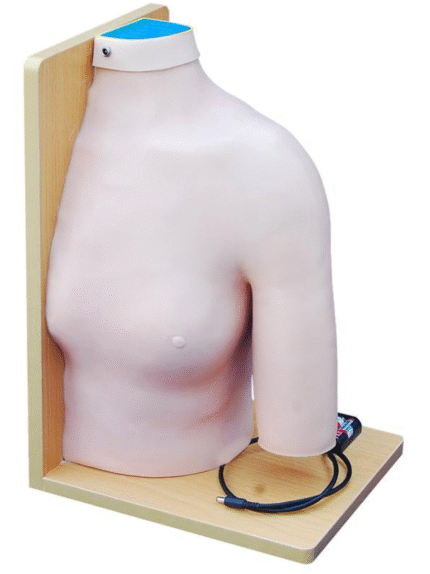

ATL-108 CENTRAL VENOUS PUNCTURE SIMULATOR SOFT

This model is divided into internal carotid artery, carotid artery, subclavian vein and femoral vein and main arteries of femoral artery. Can be used for the injection of internal jugular vein, collarbone vein and femoral vein, blood and other targeted training and the practice of long catheter intubation. This model only can simulate the pulse of carotid artery, and femoral artery, but also can locate veins.

Packing: 1pcs/carton, 92x51x23cm, 10.5kgs